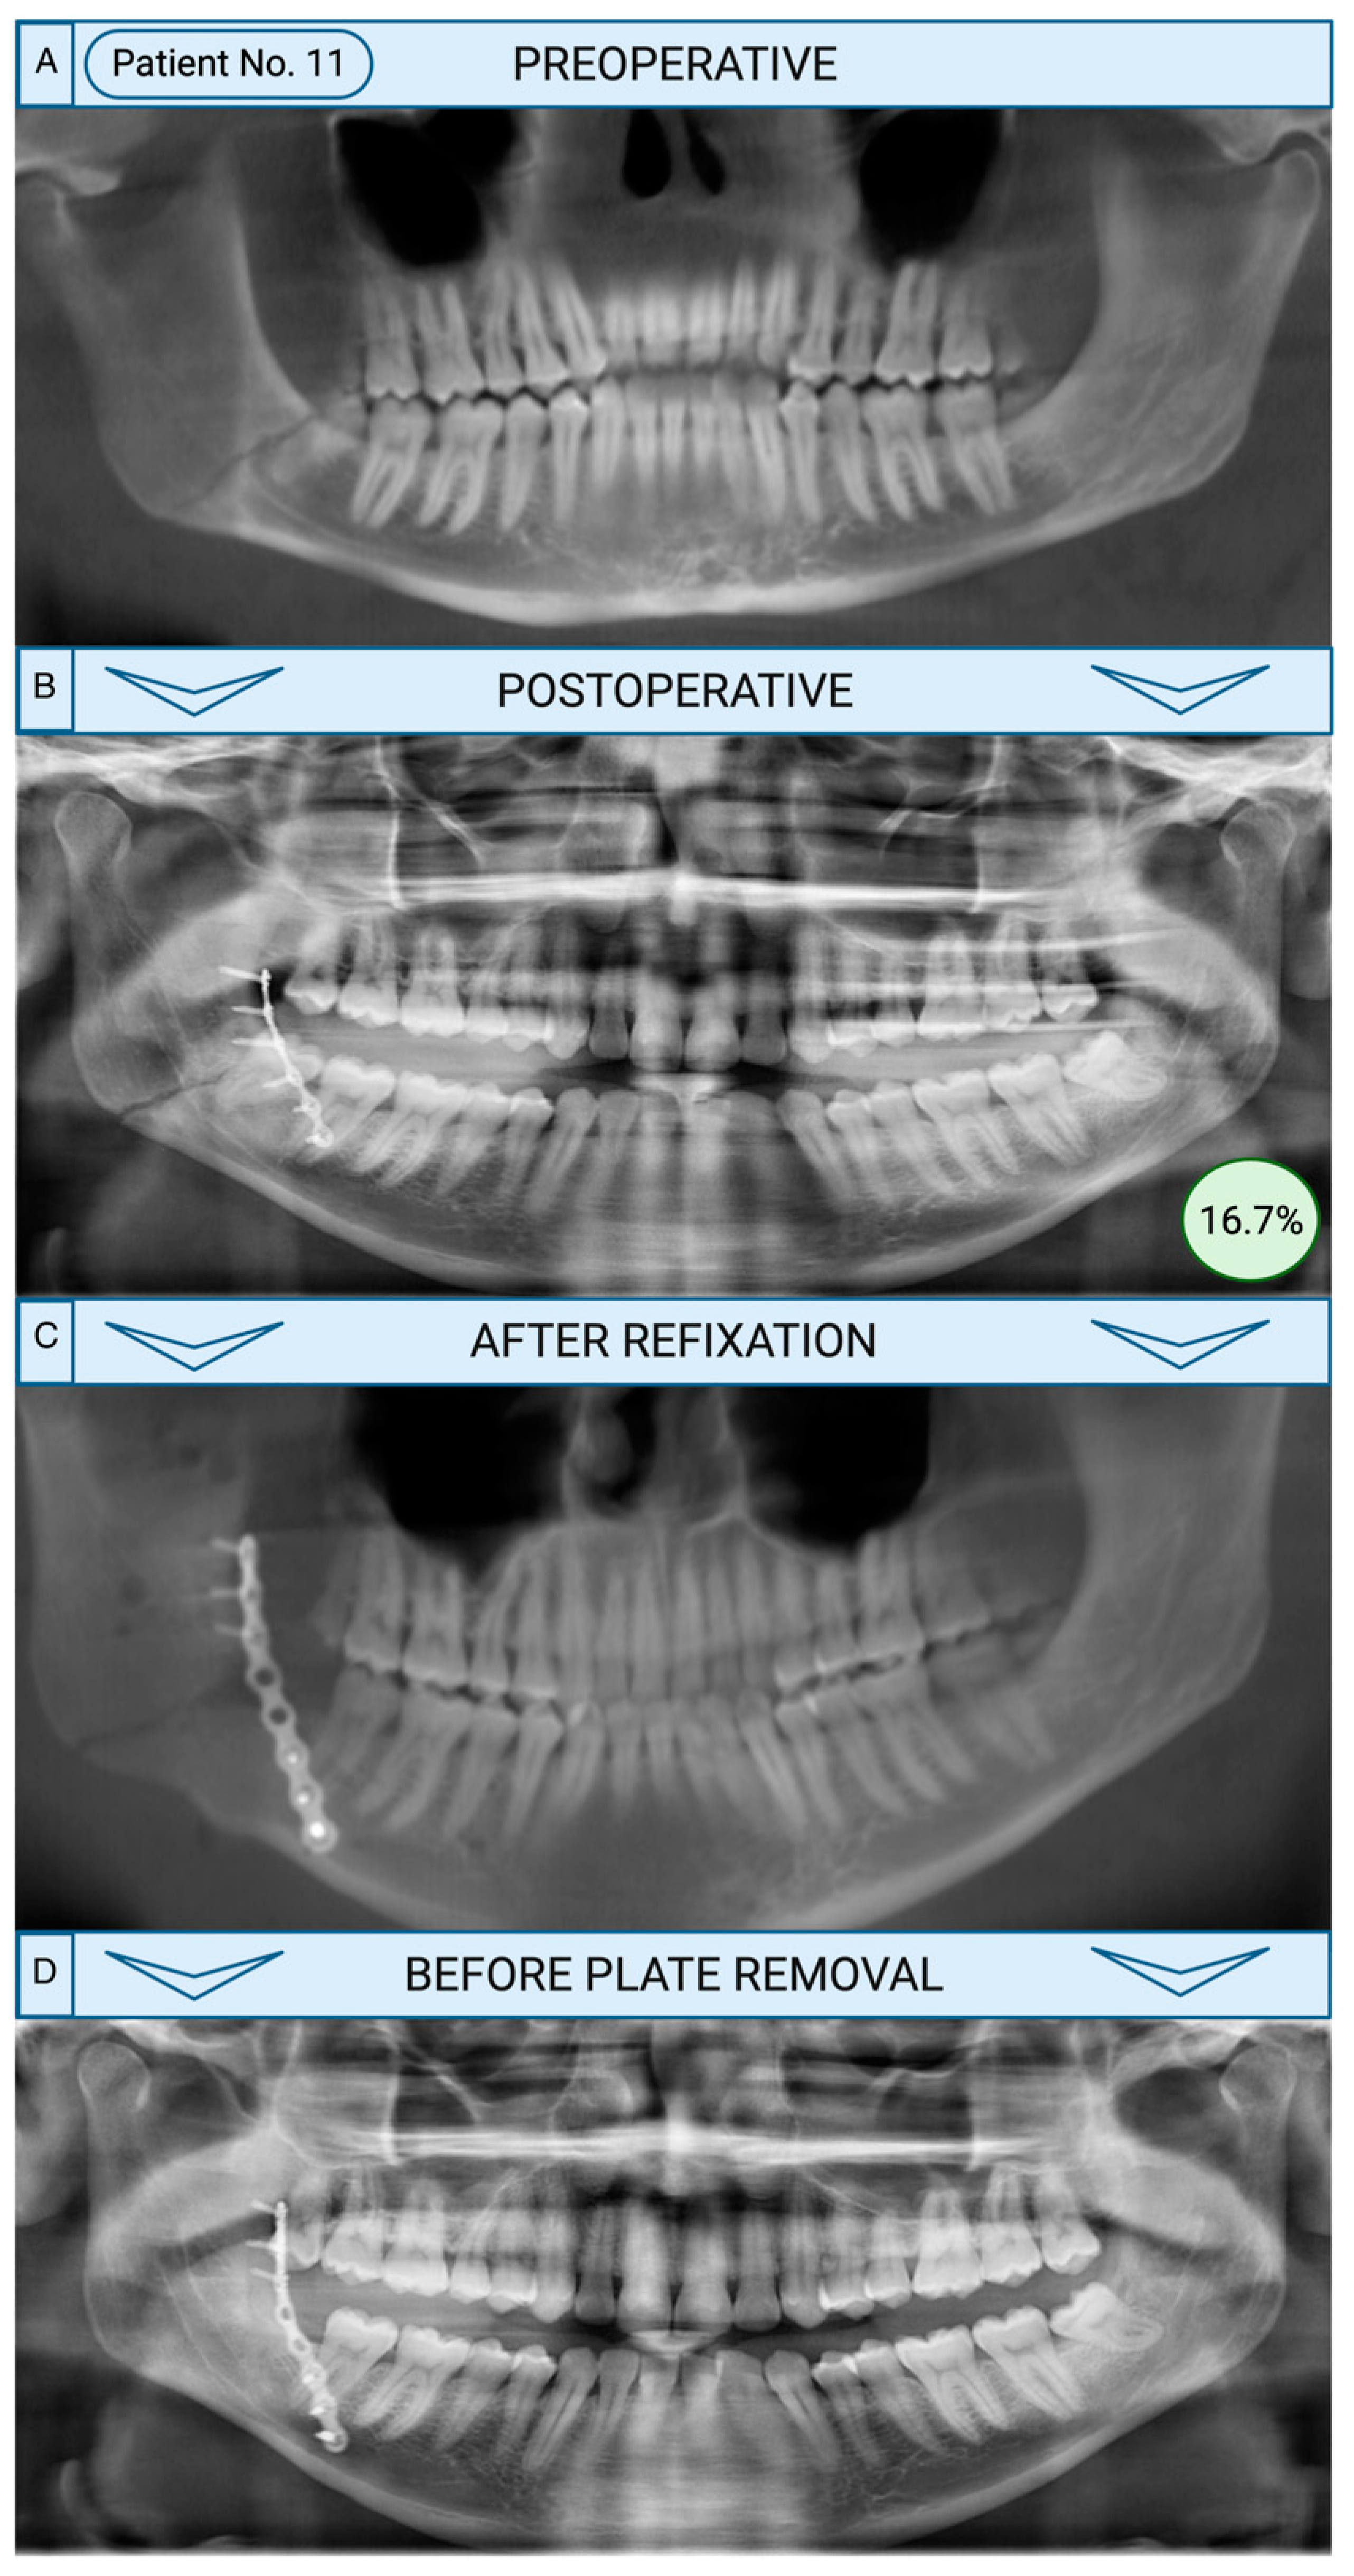

Figure 2. Revision surgery with refixation after development of complications following initial fracture treatment. A: Reconstructed cone-beam computed tomography (CBCT) demonstrates the initial fracture at the right mandibular angle in a 33-year-old male patient without risk factors. B: The patient was treated with miniplate osteosynthesis indicated by a postoperative panoramic radiograph. One specialist evaluated treatment as insufficient due to the tooth in the initial fracture gap (16.7%). C: The patient developed osteomyelitis with clinical signs of abscess formation and pain after 1 month. Consequently, tooth 48 was removed and refixation was performed as shown in the CBCT. D: Postoperative control using a panoramic radiograph after 13 months showed a sufficient osseous union. Created with Biorender.com.